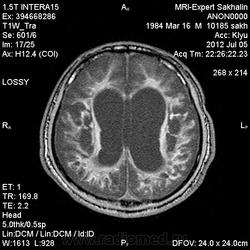

1 случай -локальная гемиатрофия.2 случай-диффузная.

Молодой человек после автомобильной аварии.3 года лежит.Двигаются только глаза.Зрелище душещипательное.

Евгений, конечно же, мои случаи не являются "чистой" атрофией-согласна.Мне пока не встречались случаи болезни Пика, Альцгеймера и другие "чистой воды" атрофии.Второй случай- состояние после длительной комы вследствие автодорожной травмы 3 года назад.Пациент проходил исследование в прошлом году , в этом родители привезли на динамику.